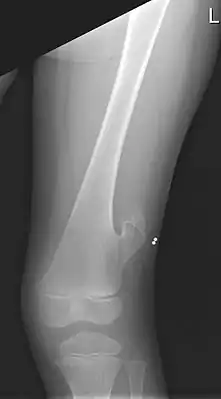

![]() Рентген левого бедра 5-летнего мальчика с экзостозом, расположенным латерально, чуть выше колена. | |